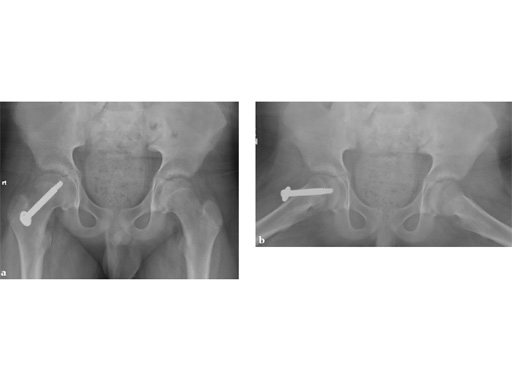

A boy aged 11 years and 3 months presented with a limp and had had pain in the thigh for 8 weeks.

Case provided by Richard Reynolds, Detroit, USA